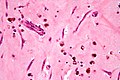

Atrial myxoma. H&E stain. | |

| LM | myxoid material (extra cellular), myxoma cells (stellate, polygonal or spindled morphology; +/-multinucleated, inconspicuous nucleoli; abundant cytoplasm), calcified elastic fibers (gamna bodies), +/-hemorrhage, +/-endothelial covering, +/-ossification, +/-fibrosis |

Microscopic

Features:[4]

- Myxoid material - extra cellular - key feature.

- Myxoma cells:[5]

- Stellate, polygonal or spindled morphology.

- +/-Multinucleated.

- Inconspicuous nucleoli.

- Abundant cytoplasm.

- Calcified elastic fibers - gamna bodies.

- Hemorrhage common.

- Often covered by endothelium.

- +/-Ossification.

- +/-Fibrosis.

The sections show paucicellular myxoid material containing polygonal and spindled cells with eosinophilic myxoid cytoplasm, bland nuclei, inconspicuous nucleoli and focal multinucleation (myxoma cells). Hemosiderin-laden macrophages, calcified elastic fibres (gamna bodies) and scattered inflammatory cells are also present. There is no nuclear atypia. Mitotic activity is not evident. Several sections show fresh hemorrhage. The edge has a fibrotic rim and appears to be covered by endothelium. No cardiac muscle is identified.